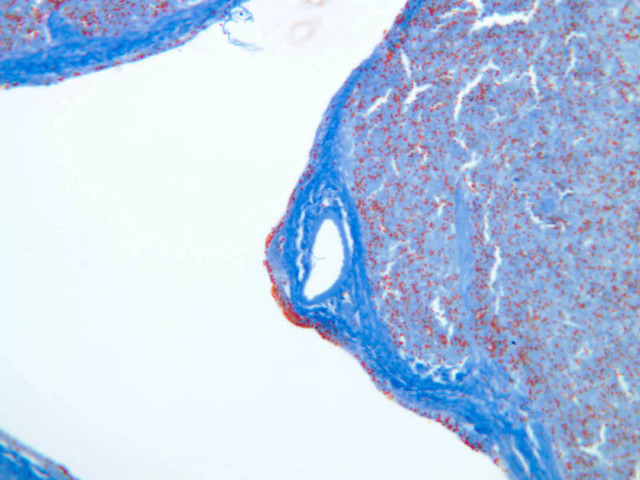

Sections through the spleen (slides A-36, aniline blue [2.5x, 10x, 20x-labeled, 40x] [2.5x, 10x-labeled, 20x-labeled, 40x]; A-37, retic [2.5x, 10x, 20x-labeled, 40x]; A- 37, H&E [2.5x-labeled, 10x, 20x, 40x]; A-38, H&E [10x, 20x, 40x]; A-39, H&E [2.5x, 10x, 20x, 40x]) show a thick investing capsule composed of collagenous tissue and smooth muscle, typically covered with mesothelium. In slide A-36 muscle and collagen are brightly stained. The capsule and mesothelium completely surround the organ and the fibrous portion enters the splenic substance at the hilus around the splenic arteries and veins forming trabeculae of fibromuscular tissue within the splenic substance. This fibromuscular tissue enables the spleen to expel blood by contracting. Identify trabeculae as fibrous partitions in the section and look for blood vessels within them.

Where the trabecular arteries pass into the splenic pulp, they become invested by a sleeve of lymphoid tissue. This lymphatic tissue collectively forms the white pulp of the spleen (A-36 [2.5x, 10x, 20x, 40x]). It also is referred to as the periarterial lymphatic sheath or PALS. On an H&E stained section (A-38 [2.5x, 10x, 20x, 40x] [2.5x, 10x, 20x, 40x]) the white pulp will appear as basophilic clumps of lymphoid cells. The arteries of the white pulp are called central arteries, although they may be displaced to one side of the lymphoid sleeve by the presence of a nodule. The majority of cells forming the PALS are T lymphocytes. In places the covering of lymphatic tissue is enlarged due to the presence of lymphoid nodules (splenic or Malphighian corpuscles) which are comprised predominantly of B lymphocytes.

Examine the composition of the red pulp tissue. The three dimensional structure of the red pulp is analogous to Swiss cheese with the holes being the venous sinuses and the cheese being the parenchyma (i.e. splenic cords). On slide A-36 which is stained with Mallory's aniline blue locate examples of the splenic sinuses ([2.5x, 10x, 20x, 40x-labeled] [10x, 20x, 40x]). The walls of the splenic sinuses consist of adjoining specialized endothelial cells whose nuclei in many cases stand out from the wall in a bead-like fashion. The basement membrane of the epithelial cells stains blue revealing the sinuses quite nicely. Usually the sinus lumen is filled with red cells and leukocytes. The skeletal framework of the cords is provided by a network of reticular fibers. As above, the reticular cells are best seen using a reticular fiber stain (slide A-37 [2.5x, 10x, 20x, 40x-labeled]). Look for the large pale nuclei of reticular cells that have darkly stained reticular fibers. Fibers run irregularly in the cords, but clearly outline the sinuses around which they are wrapped. Notice on this same slide that there is much less reticular tissue in the white pulp than the red. The splenic cords occur around the sinuses and are distinguished by the presence of disintegrating red blood cells undergoing phagocytosis.